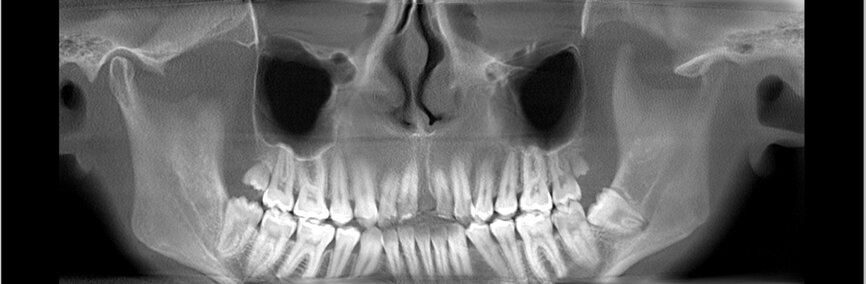

W dniu wizyty w poradni brak było oznak ostrego stanu zapalnego w okolicy 12-11. Widoczne były recesje dziąsła o wysokości 2 mm po stronie wargowej na zębach siecznych górnych przyśrodkowych, zmniejszona wysokość dziąsła zrogowaciałego do wartości 2 mm, spłycony przedsionek (Ryc. 1). Zęby były tkliwe na opukiwanie pionowe i poziome oraz wykazywały I stopień rozchwiania wg Entina. W przekrojach TK widoczny był rozległy przewlekły stan zapalny wokół wierzchołków korzeni zębów 11 i 21 (Ryc. 2), brak blaszki przedsionkowej wyrostka zębodołowego szczęki oraz resorpcja korzeni. Po wnikliwej analizie stanu miejscowego i rozmowie z rodzicami zadecydowano o ekstrakcji zębów 11 i 21 oraz w drugim etapie, ze względu na rozległy i zaawansowany proces zapalny, o autotransplantacji zawiązków 35 i 45.

Ryc. 2_TK przedzabiegowe.